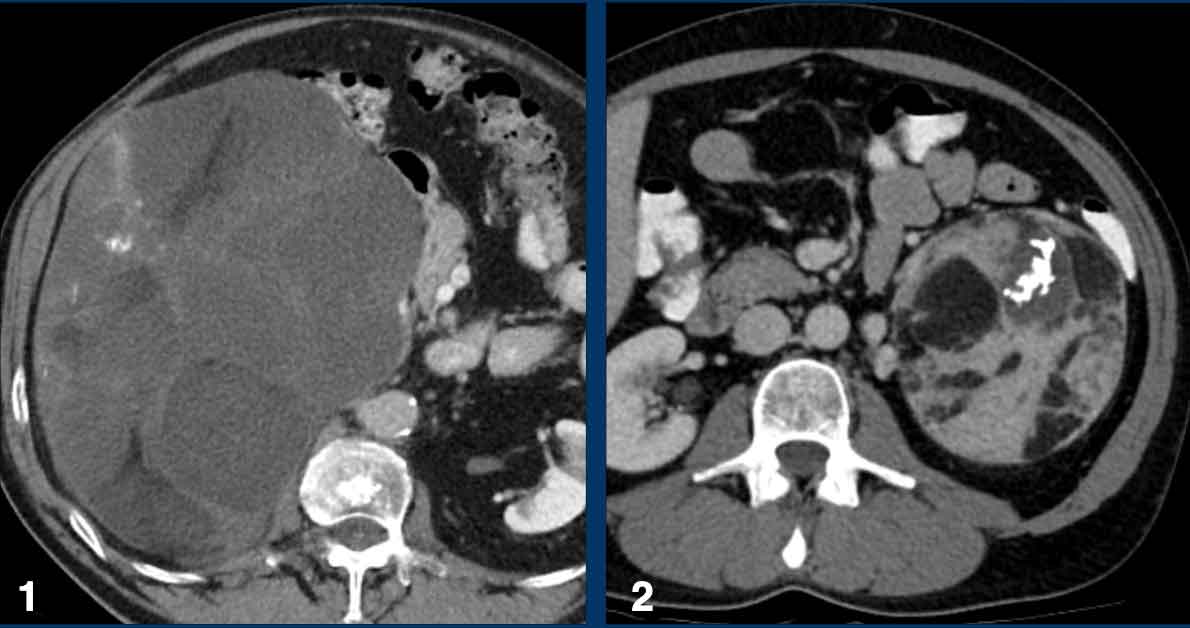

The image shows a 67 mm heterogeneously enhancing relatively well defined lesion.

This proved to be an adrenocortical carcinoma, after resection.

This is a heterogeneously enhancing, relatively well-defined indeterminate lesion.

It proved to be a pheochromocytoma.